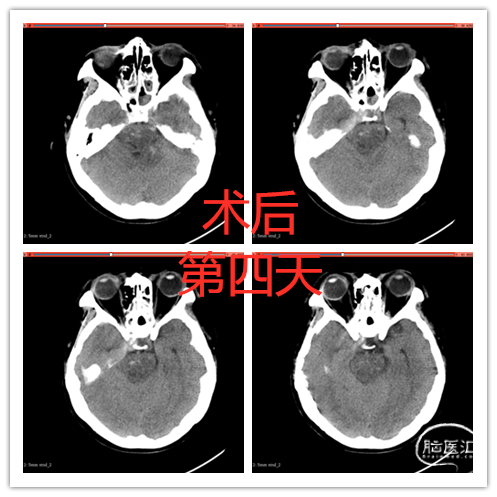

术后1周患者转醒,自主睁眼,能按吩咐活动左侧肢体,左上肢肌力3级。有轻度左侧面神经功能障碍,静息状态下闭眼完全。(详见视频)